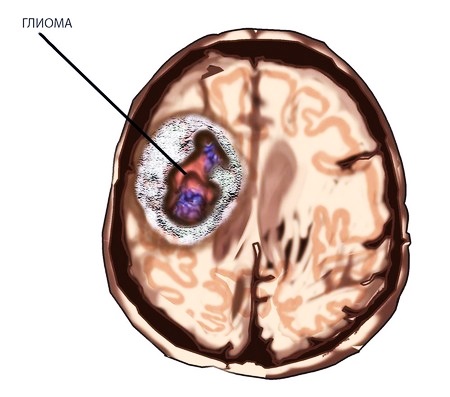

Чаще всего глиома головного мозга единична. Может наблюдаться диффузное поражение, развитие отека. Располагается она в преимущественном большинстве ситуаций в сером либо белом веществе головного, спинного мозга. Новообразования могут крайне близко находиться возле центрального канала и стенок желудочков. В периферических нервах образования локализуются намного реже.

Опухоль может иметь различный размер – от размера зернышка до габаритов яблока. Все очень индивидуально. В любом случае жизнь пациентов оказывается под угрозой.

По форме глиома напоминает шар, реже – веретено. Растет она достаточно медленно. Заболевание может развиваться на протяжении нескольких лет. При возникновении глиобластомы метастазы не появляются. Прогнозирование сугубо индивидуально.

Опухоль может быть первичной (неокклюзионной) и вторичной (окклюзионной).